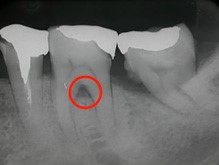

右の写真をご覧ください。赤丸で囲んだ部分が黒くなっています。ここは、歯茎が衰え歯と歯茎の間にできたすき間です。ここに付着した歯石は取り除くことができず、そのまま放置すると歯周病が進行して、やがて抜歯となってしまいます。